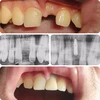

Zirkonyum uygulamalar

Porselen uygulamaları

Laminate veneer